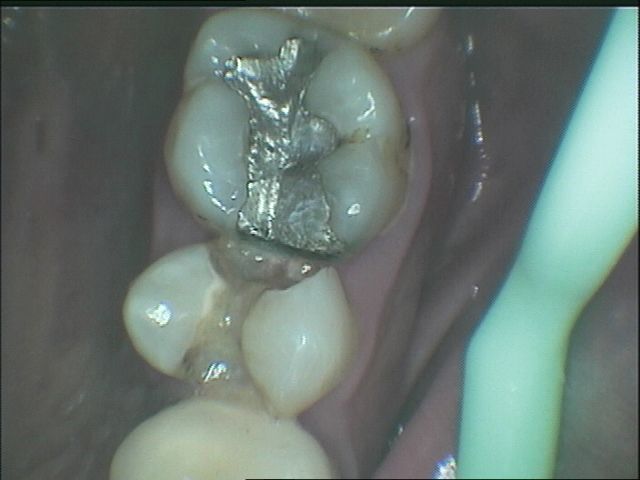

傳統金屬材料(銀粉)會熱脹冷縮,而且無法與琺瑯質連結在一起,太大的缺損在填補後經過一段時間容易與牙齒分開,導致二度蛀牙,導致齒質再破壞。

圖2較大的蛀洞可使用3D齒雕,保存較多牙齒結構,並提供足夠強度的支撐,恢復牙齒型態與功能。